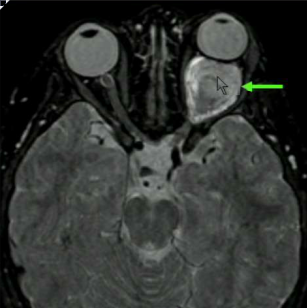

What structure is indicated in the T2 image below?

Middle cerebellar peduncles. Note that most of the white matter (which is dark on FLAIR) from the MCP makes up the core of the cerebellum.